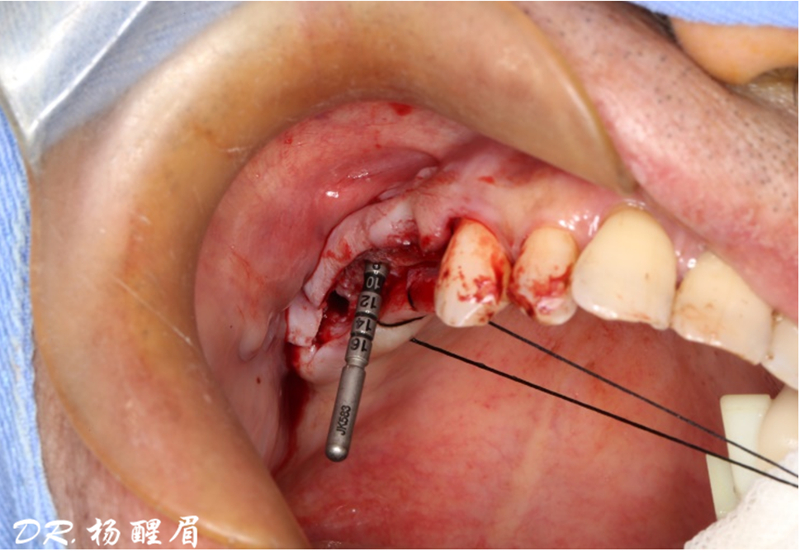

®完成標定及配準

®按照術前方案進行備洞及植體植入

®按照術前方案進行備洞及植體植入,醫(yī)生可以通過屏幕軟件引導對手術中植入點、角度、深度實時追蹤

®對植體深度及方向進行確認